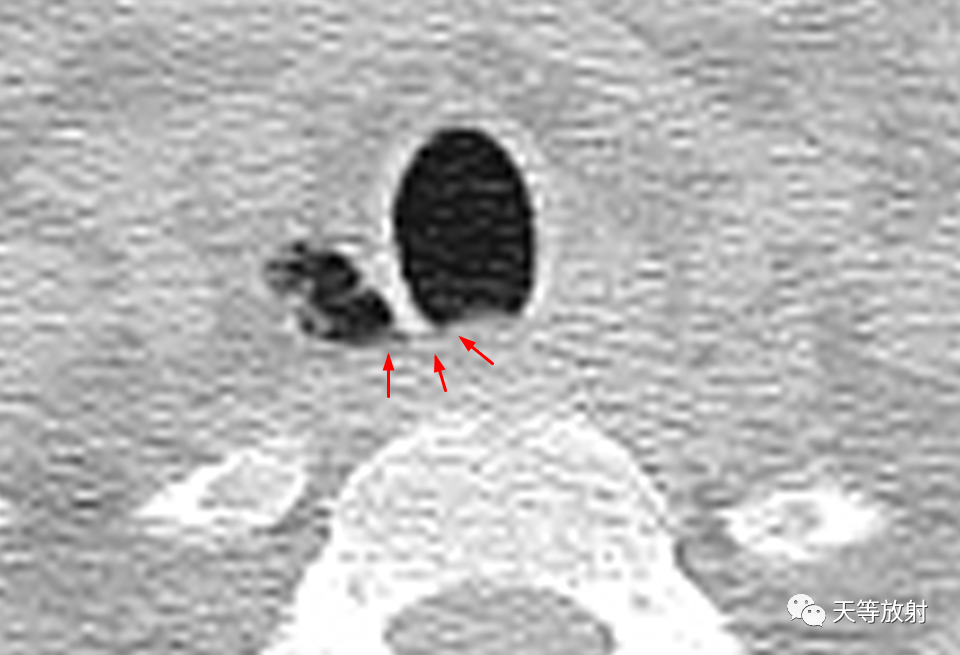

上图:胸廓入口处气管旁纵隔内局限含气影,复查片显示含气影内见细小分隔,囊影内壁较光整。

上图:CT值囊影与气管内气体CT值相同,为气体密度影。

薄层CT并放大观察,胸廓入口处气管旁纵隔内局限含气影,可见细线样低密度影与气管交通。